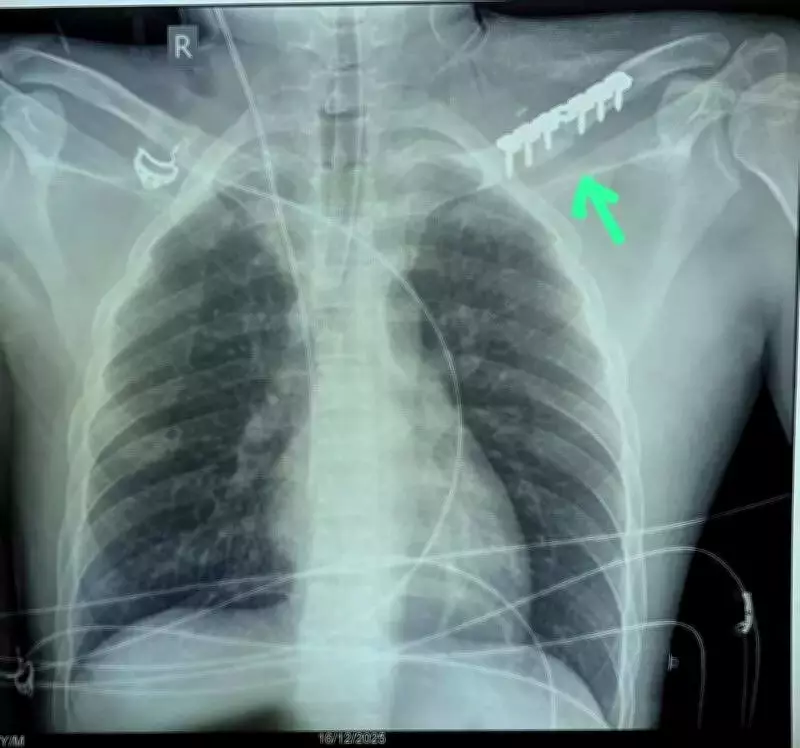

The subclavian artery presents a formidable surgical challenge due to its location deep within the chest cavity. To reach the injury site, a multidisciplinary medical team was assembled under the leadership of Dr Krishnakant Sahu, Head of the Department of Heart, Chest and Vascular Surgery. Orthopedic surgeons assisted by cutting the clavicle (collarbone), providing the necessary access for the vascular team to address the damaged artery.

During the meticulous four-hour operation, surgeons discovered a 3-centimeter section of the artery had been completely destroyed. They skillfully replaced this damaged segment with a 7x30 millimeter Dacron artificial vascular graft to restore proper blood circulation. The patient required five units of blood during this marathon surgery.

The surgical team took extraordinary care to protect the brachial plexus nerve bundle during the procedure, preventing potential permanent paralysis. Once the vascular repair was successfully completed, the orthopedic team meticulously re-fixed the clavicle using a metal plate for stabilization.